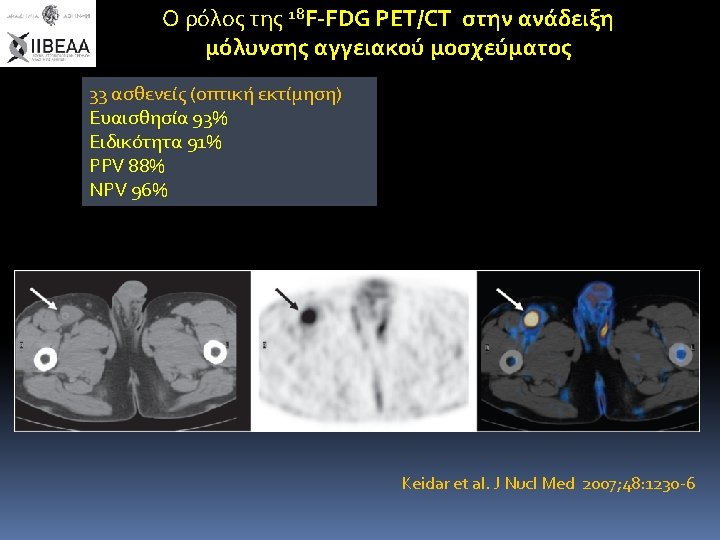

Ο ρόλος της 18 F-FDG PET/CT στην ανάδειξη μόλυνσης αγγειακού μοσχεύματος 25ασθενείς Ευαισθησία 93%

Ο ρόλος της 18 F-FDG PET/CT στην ανάδειξη μόλυνσης αγγειακού μοσχεύματος 25ασθενείς Ευαισθησία 93% Ειδικότητα 70% PPV 82% NPV 88% FDG PET analysis (four point scale) Grade Ι: uptake ≤ background (-) Grade II: uptake ≤ soft tissue (-) Grade III: moderate uptake ≥ soft tissue (+) Grade IV: strong uptake comparable with bladder (+) Brukking et al. Eur J Vasc Endovasc Surg 2010; 40, : 348 -354